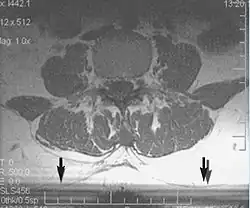

Metal artifacts

Metal artifacts occur at interfaces of tissues with different magnetic susceptibilities, which cause local magnetic fields to distort the external magnetic field. This distortion changes the precession frequency in the tissue leading to spatial mismapping of information. The degree of distortion depends on the type of metal (stainless steel having a greater distorting effect than titanium alloy), the type of interface (most striking effect at soft tissue-metal interfaces), pulse sequence and imaging parameters. Metal artifacts are caused by external ferromagnetics such as cobalt containing make-up, internal ferromagnetics such as surgical clips, spinal hardware and other orthopaedic devices, and in some cases, metallic objects swallowed by people with pica.[3] Manifestation of these artifacts is variable, including total signal loss, peripheral high signal and image distortion (Figs 3 and 4).[1] Reduction of these artifacts can be attempted by orientating the long axis of an implant or device parallel to the long axis of the external magnetic field, possible with mobile extremity imaging and an open magnet. Further methods used are choosing the appropriate frequency encoding direction, since metal artifacts are most pronounced in this direction, using smaller voxel sizes, fast imaging sequences, increased readout bandwidth and avoiding gradient-echo imaging when metal is present. A technique called MARS (metal artifact reduction sequence) applies an additional gradient, along the slice select gradient at the time the frequency encoding gradient is applied.